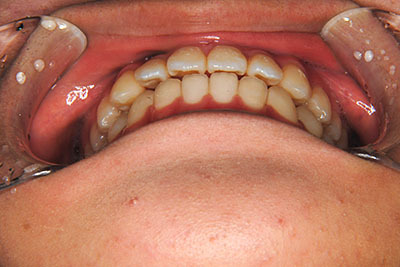

歯が乳歯から永久歯に生え変わった小学生高学年や、中高生でも矯正治療に手遅れということは全くありません。

成長中の顎の骨を矯正できたり、この時期の矯正はおとなになってから矯正治療を始めるよりも短期間で済むことがほとんどです。当院だとおおよそ1年で動的治療(マルチブラケット装置をつける期間)が終わることが多いです。